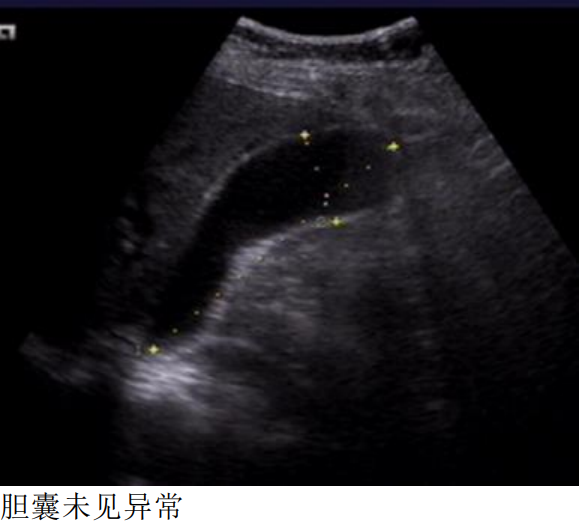

余留森 广东省中山市人民医院南朗分院 病史:女,72岁,上腹部疼痛2天 一、早晨8点,超声检查

DWI胆囊内病变呈高信号,ADC值下降,提示弥散受限。 LAVA-FLEX四像图:水像病变呈等低信号,脂肪像低信号,同反相位未见显著信号改变,提示病变不含大量脂肪成分。 小朋友,你是否也有很多问号? 超声,CT都提示胆囊未见异常。 MR发现胆囊里面这么大一坨东西。 它是什么,它来自哪里,它会去向何方? 没有伪影的MR是不正常的,机器问题,参数问题? 四、晚上18点,超声复查

五:胆泥 胆泥是胆汁中的为微观沉淀物,由黏蛋白、胆固醇晶体、胆红素钙盐和其他钙盐组成,可随体位变化移动,超声胆泥后方无明显声影。